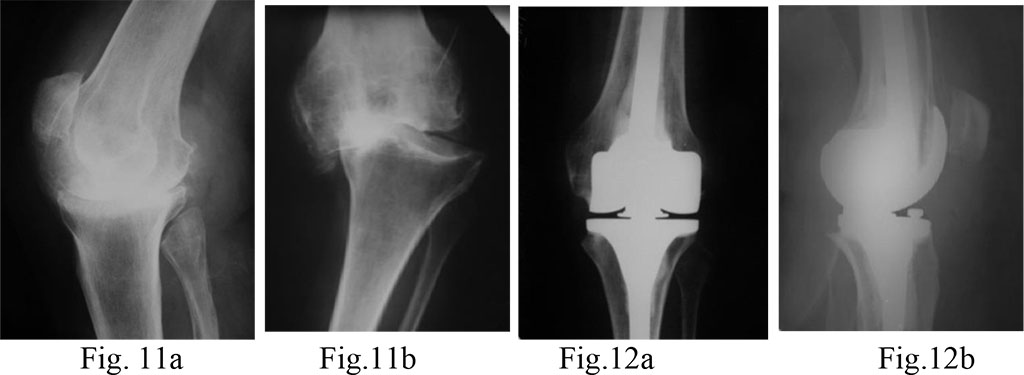

Diagnosis: a posttraumatic gonarthrosis stage 4 on the left; varus deformity of the left knee; the frontal instability; complete lateral knee stabilizers’ incompetence.

Surgical treatment: total knee arthroplasty on the left with a constrained hinge-type endoprosthesis (Fig. 11a, b and 12a, b)